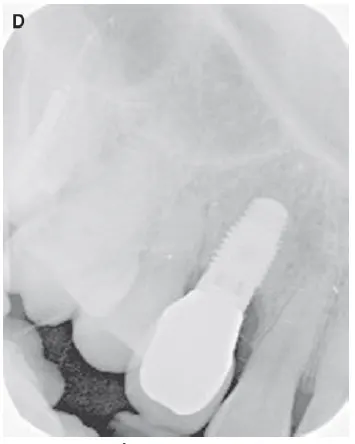

شکل VII‑8 (ادامه)

شکل VII‑8 (ادامه): رادیوگرافی نهایی D